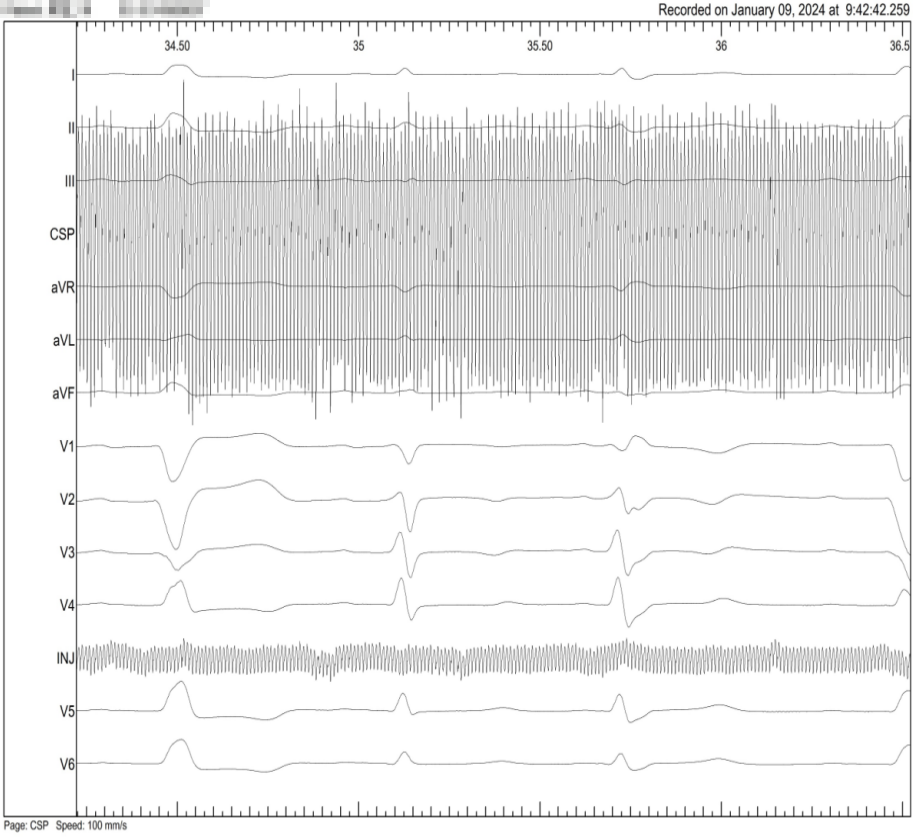

术前患者自身心电图LBBB,QRS宽度168ms

术中HIS电位H-V50MS

HBP起搏后高输出纠正LBBB

LBB电极术中传导束PVC

LBBP 术中S-NS变化

最终融合QRS

LBBB患者术前

LBBP NS

LBBP S

术后融合:DDD SAV:120,单LV双极起搏 2.5V输出

术前自身

HIS

HISD电位

HISD 电位损伤